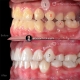

درمان ارتودنسی در کیس کلاس ۲ همراه با جلوزدگی فک بالا و کراودینگ شدید دندانی در فک بالا در مدت ۲۰ ماه

Orthodontic treatment of class 2 case with prognathic maxilla and sever crowding in upper arch done within 22 months.